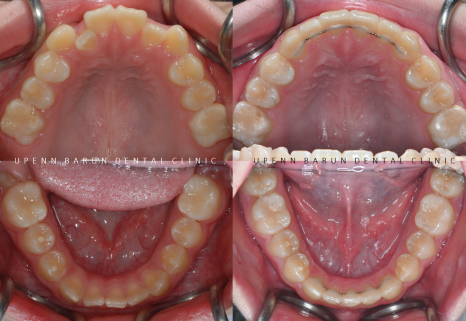

교정기간: 23/8 ~ 24/11

마지막 클린체크인 12개의 장치를 통해 교정이 마무리된 사진입니다.

송파다이아몬드등급치과

유펜바른치과에서

김원장님의 세심한 진료와 환자분의 높은 협조도로

발치 하지 않고 반대교합을 개선하고

치열을 가지런하게 마무리 해드렸습니다.

앞니의 반대교합이 있고

치열이 고르지 않아

송곳니가 도드라져 보였던 이전과는 달리,

청소년기 인비절라인 교정 후 치열이 가지런해지면서

보다 정돈된 이미지를 줍니다.